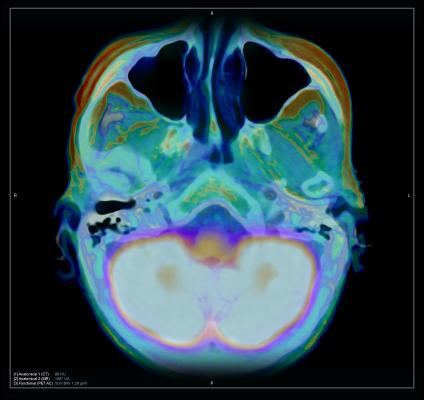

Cat Scan Brain Tumor